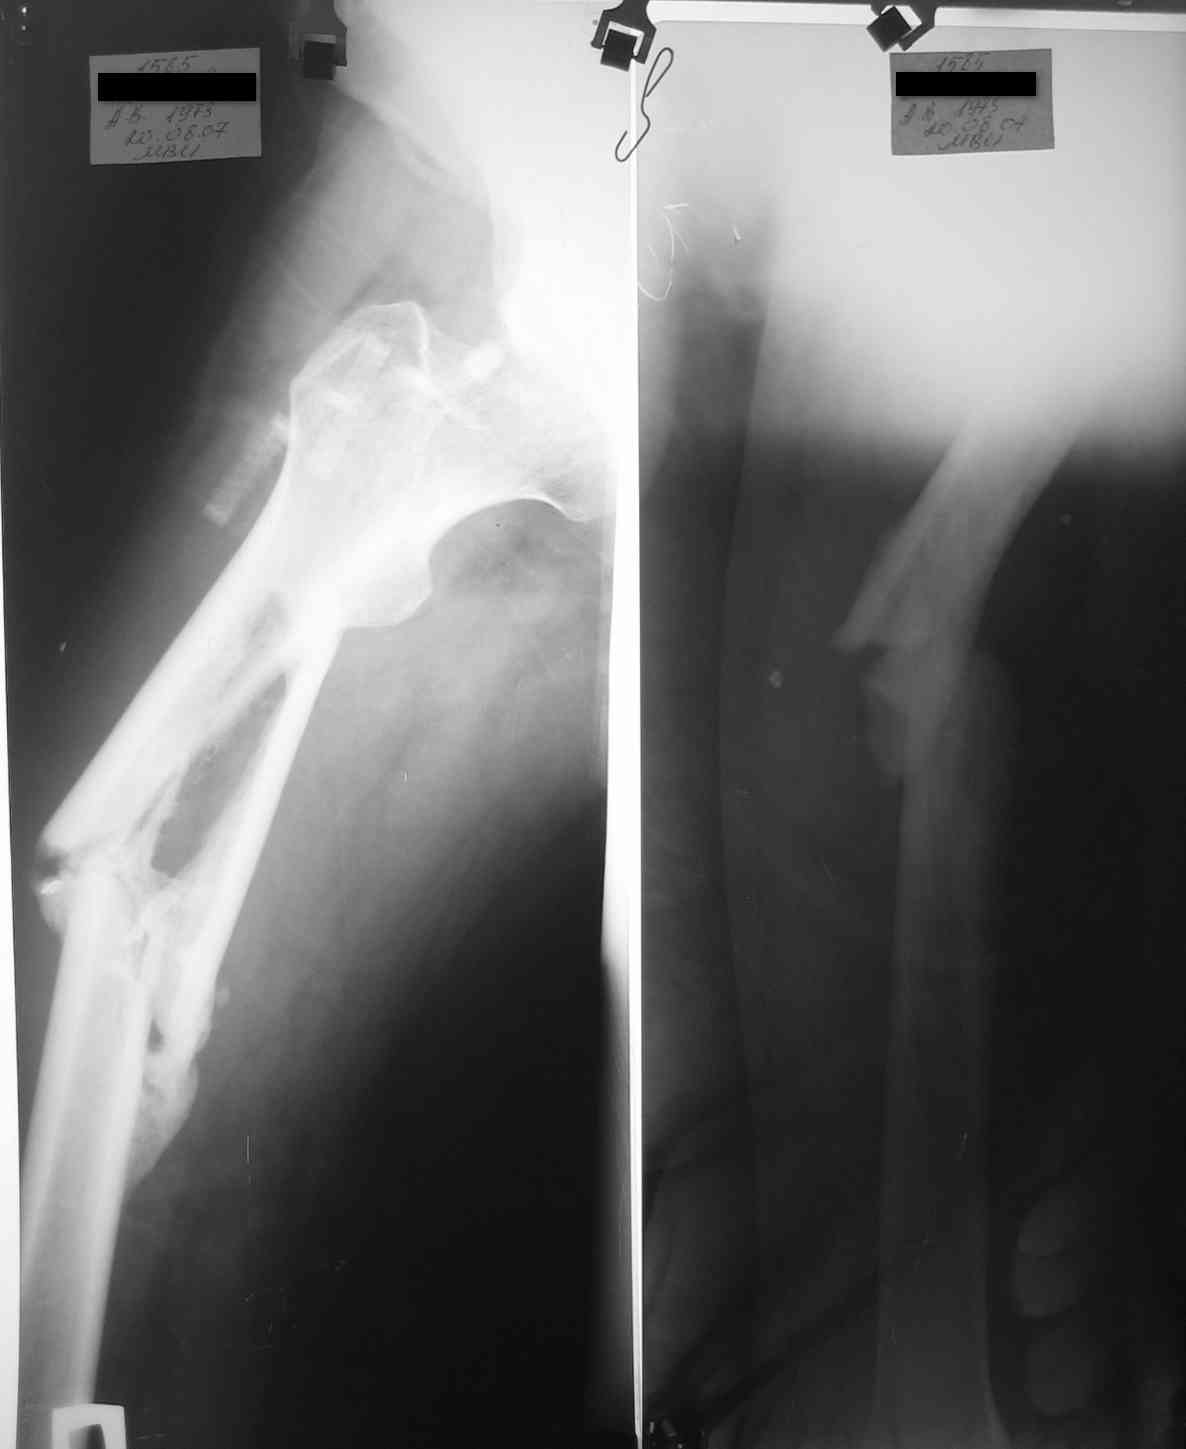

уважаемые коллеги, поступил пациент, через 6 месяцев после травы, который лечлся скелетным вытяжением на районе 3 месяца

затем гипс еще 1,5 месяца, дозированная нагрузка через 3,5 месяца после травмы. Дней 5 назад поскользнулся в ванной, почувствовал боль в бедре, появилась деформация. Оперирован у нас, произведен остеосинтез блокирующим стержнем ,перелом не открывался, был "доломан" на столе. меня интересует вариант вальгирования гвоздя в этом случае. И по-вашему какие ерспективы у этого клиента?

Учитывая отсутствие медиальной стенки на большом протяжении, действительно, мог быть варус при латеральном заходе. Но удалось вполне неплохо справиться, можно поздравить. Из дополнительных мер - точку входа надо делать чуть медиальнее, и можно ввести спицу спереди назад над дефектом, чтобы гвоздь оттеснить к латеральной стенке канала.